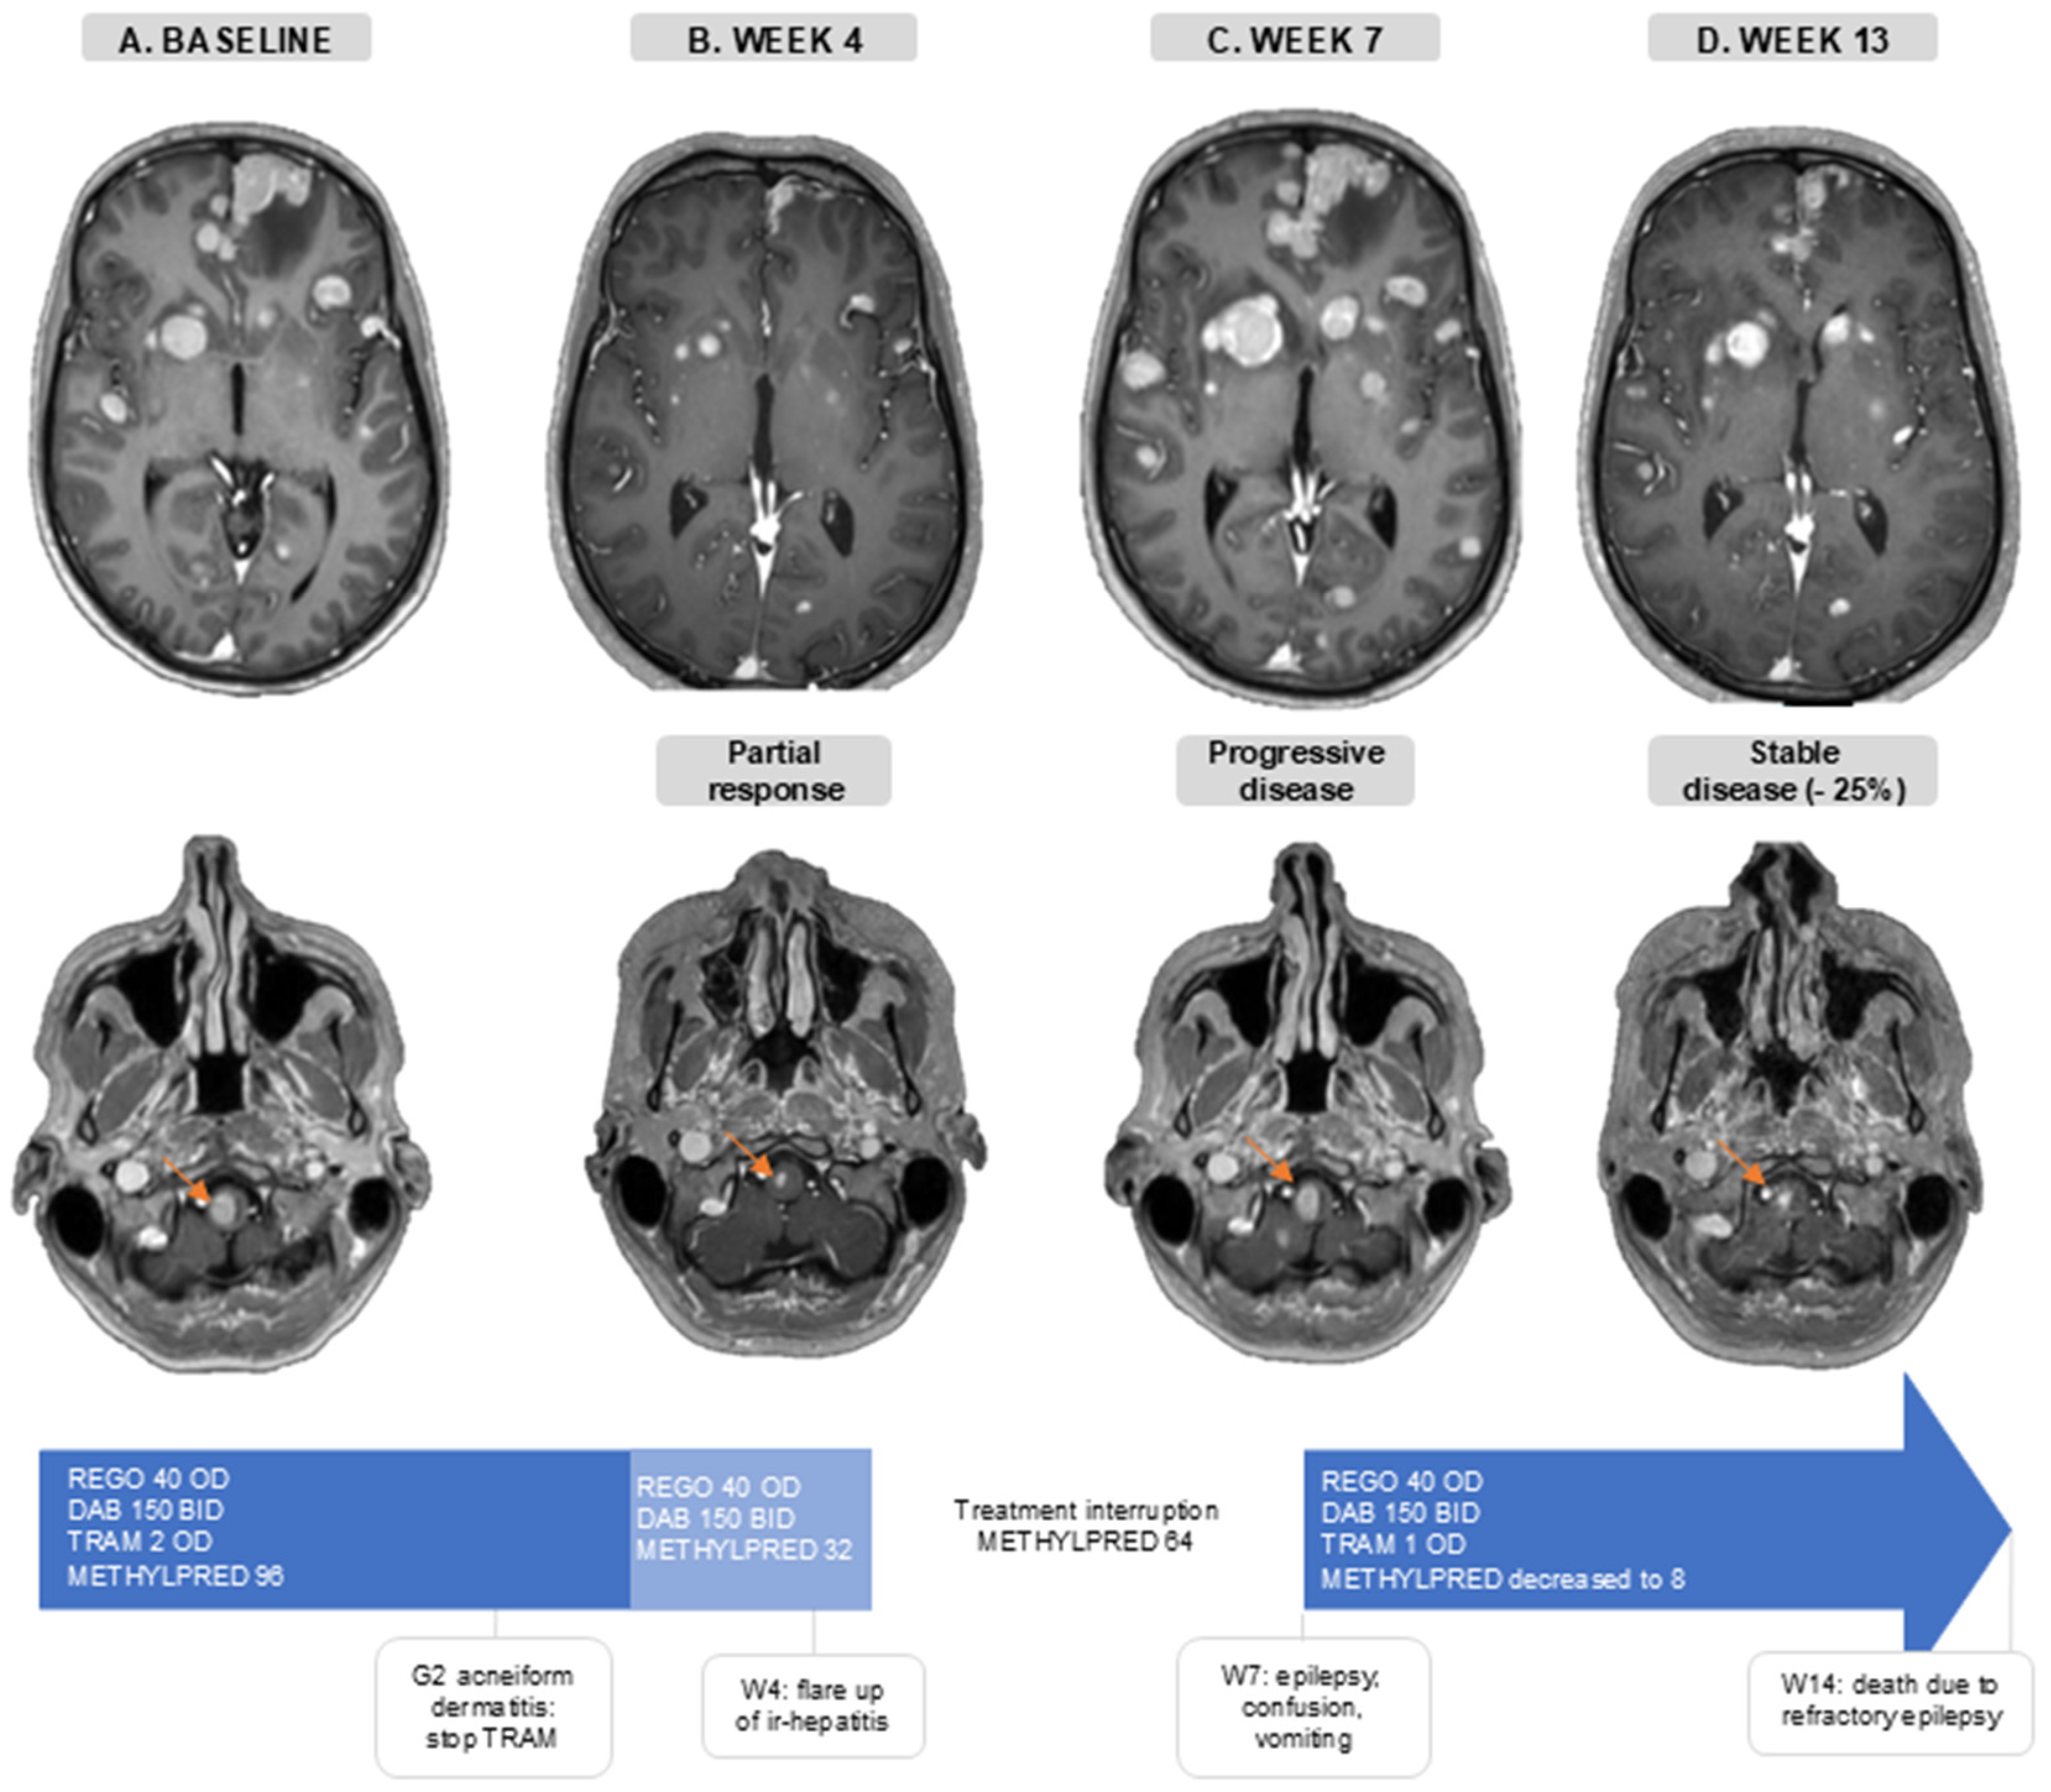

3.6. Case Illustration